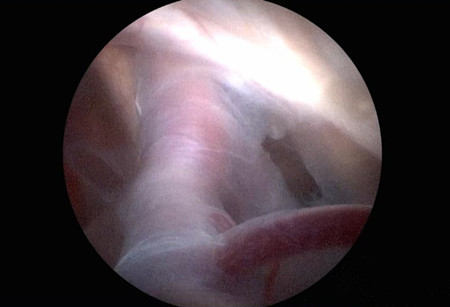

(1)若中颅窝蛛网膜囊肿与基底池临近,选择颞部钻孔内镜下囊肿-脑池造瘘术。患者多采用侧卧位,摆好头位,切口设计于颞部发际内,避开面神经颜支的走行,将颅骨钻孔位置放置于最高点,避免脑脊液外流和气体进入颅内。内镜进入囊肿腔后,内侧造瘘于脚间池、视交叉池或颈内动脉池。

(2)对于不能和基底池沟通、体积较小、有症状、位于颞极的蛛网膜囊肿可选择经眉弓外侧入路。在额叶和前颅底之间置入神经内镜,沿眶顶和蝶骨小翼到达侧裂,行囊肿-鞍上池、脚间池造瘘术。